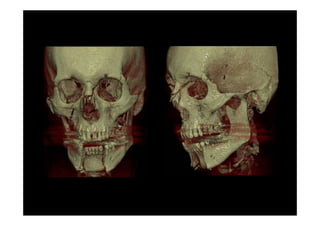

Fracturas complejas de la cara

Fracturas complejes de la cara

Fracturas Cigomáticas Complejas

Fracturas Órbito-craneanas

6 traumatismos faciales